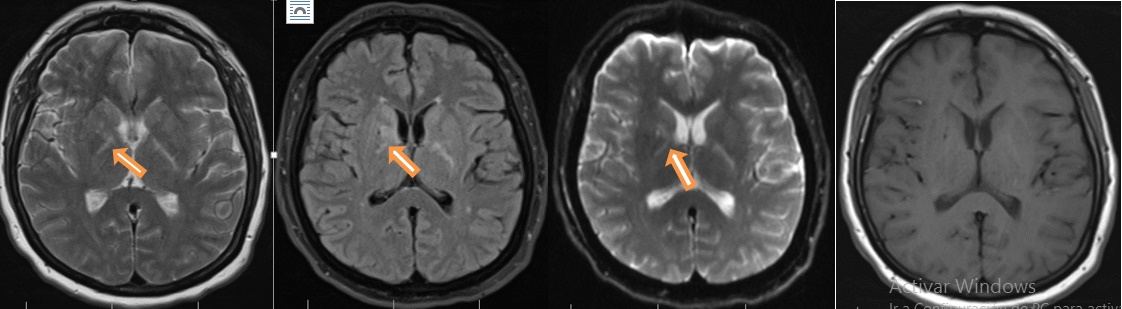

Forty-nine-year-old female, previously healthy, was experiencing working memory loss, disorientation, inappropriate behaviour, structured visual hallucinations, and finally myoclonic seizures, which increased progressively to epilepsy encephalopathy. Infectious and neoplastic causes were ruled out. EEG for twelve hours showed continuous slowdown without adequate sleep patterns, not interictal findings (Figure 2). An immunologic cause was confirmed with a cerebral MRI showing inflammatory process described as T2 hyperintense lesions in right basal ganglia with diffusion-restricted imaging (Figure 3).

Figure 3 Hyperintense lesions on T2 and Fluid attenuated inversion recovery (FLAIR) MRI image that compromised the basal ganglia right side with restricted diffusion, no lesion enhancing.

In cases of antibodies against NMDA-R, pathology can be documented by inflammatory changes as hyperintense lesions in T2 that restrict dissemination in neocortical region, basal ganglia, temporal mesial, or brainstem up to 33% as what happened with our patient who had positive anti NMDA-R.14,15